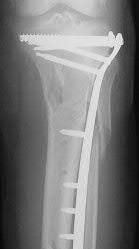

A 25-year-old female is involved in a motor vehicle collision. She presents with the isolated injury seen in Figures A through D. Her leg is swollen but her skin is intact. She has no clinical signs of compartment syndrome. Which of the following treatment options will allow for maintenance of fracture alignment and minimize the risk of soft tissue complications?

The patient presents with a closed distal third metaphyseal-diaphyseal distal tibia fracture with simple intra-articular extension. Immediate intramedullary nailing along with percutaneous fixation of the articular component provides appropriate restoration of length, rotation and alignment and minimizes the risk of wound complication.

Displaced distal third tibia fractures may be associated with simple intraarticular extension. Operative treatment of intra-articular distal tibia fractures has historically been performed with open reduction and internal fixation. Early open reduction and plate fixation of pilon fractures has been associated with high rates of infection and wound complication. In select patterns with simple articular extension, percutaneous screw fixation and medullary nailing may provide appropriate reduction with minimal soft-tissue risk.

Marcus et al. evaluated the outcomes of immediate intramedullary nailing and percutaneous fixation of simple intra-articular distal tibia fractures (AO/OTA 43 C1 and C2). The authors found excellent rates of union and alignment, however caution against broad application of this technique until more rigorous randomized studies can be performed.

Figures A and B demonstrate a distal third tibial shaft fracture with simple intra-articular extension. The axial and coronal CT cuts in Figures C and D further clarify the articular injury. Illustrations A and B demonstrate a comminuted distal third tibial fracture with simple intra-articular extension. Illustrations C and D are fluoroscopic images of the same injury after intramedullary nailing and percutaneous fixation of the articular component.